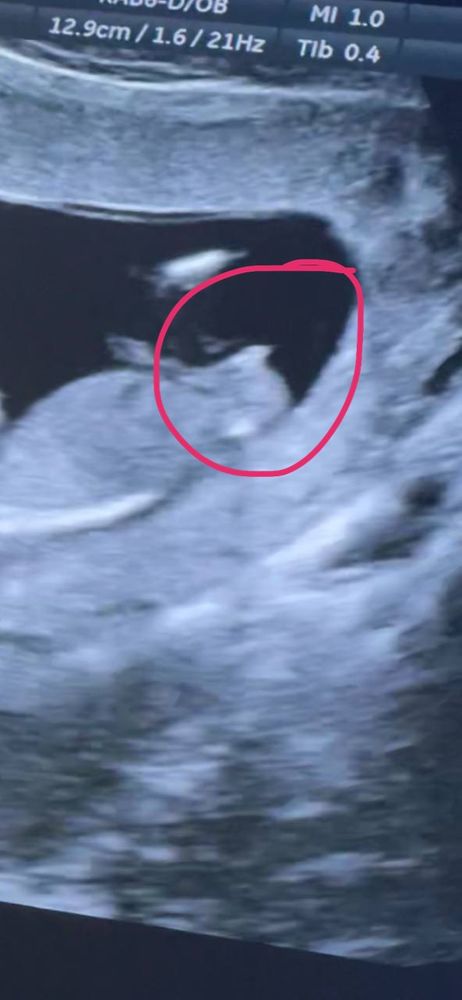

Наш первый скрининг 13 недель. Мальчик или девочка?

Девочки, как думаете, по бугорочку, кто у нас ?)) на видео везде он одинаковый со всех ракурсов, поэтому хочу почитать ваши предположения 🥹

извините за качество, скринила с видео))

Вроде больше на девочку похоже, бугорок лежит) у нас в свое время голосование разделилось))) многие девочку увидели,а ждём мальчика))) сходите ,попросите на 16-17 неделе

На таком сроке вроде всё одинаково, только угол наклона разный, у мальчиков более вертикально, предположу девочку😊